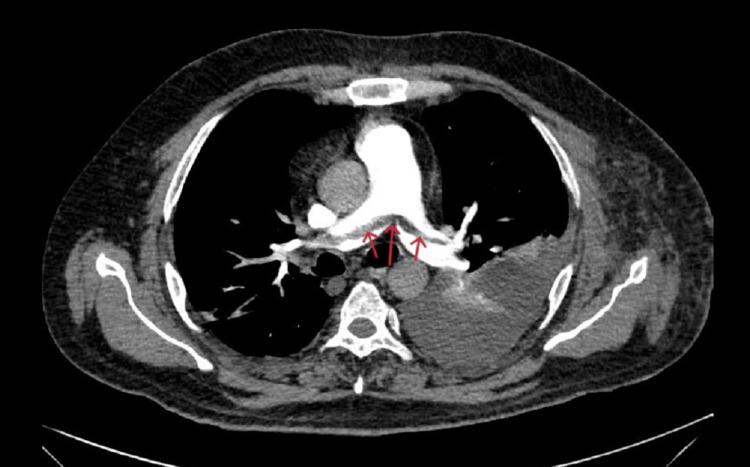

Acute pancreatitis (AP) is an inflammatory condition with varied clinical presentations. Local complications include peripancreatic fluid collection, acute necrotic collection, walled-off necrosis, and pancreatic pseudocyst, but vascular complications like pseudoaneurysm and venous thrombosis are also reported. Patients often experience splanchnic venous thrombosis, which can affect the splenic vein, portal vein, and superior mesenteric vein individually or in combination. Rarely, extra-splanchnic venous thrombosis, including renal vein, superior vena cava, and inferior vena cava thrombosis, has been reported in cases of chronic pancreatitis. The formation of a venous thrombus in acute pancreatitis is multifaceted, with pancreatic inflammation and the immune response mounted by the patient playing a significant role. There is a dearth of medical literature regarding extra-splanchnic venous thrombosis and the use of therapeutic anticoagulation in the successful treatment of the above-mentioned complication. This case report highlights the rare complications that can be seen in cases of acute pancreatitis.

急性胰腺炎(AP)是一种临床表现多样的炎症性疾病。局部并发症包括胰周液体积聚、急性坏死性积聚、包裹性坏死和胰腺假性囊肿,但也有报道称存在诸如假性动脉瘤和静脉血栓形成等血管并发症。患者常发生内脏静脉血栓形成,可单独或联合累及脾静脉、门静脉和肠系膜上静脉。在慢性胰腺炎病例中,罕见报道有包括肾静脉、上腔静脉和下腔静脉血栓形成在内的内脏外静脉血栓形成。急性胰腺炎中静脉血栓的形成是多方面的,胰腺炎症和患者的免疫反应起了重要作用。关于内脏外静脉血栓形成以及使用治疗性抗凝剂成功治疗上述并发症的医学文献较少。本病例报告突出了急性胰腺炎病例中可能出现的罕见并发症。